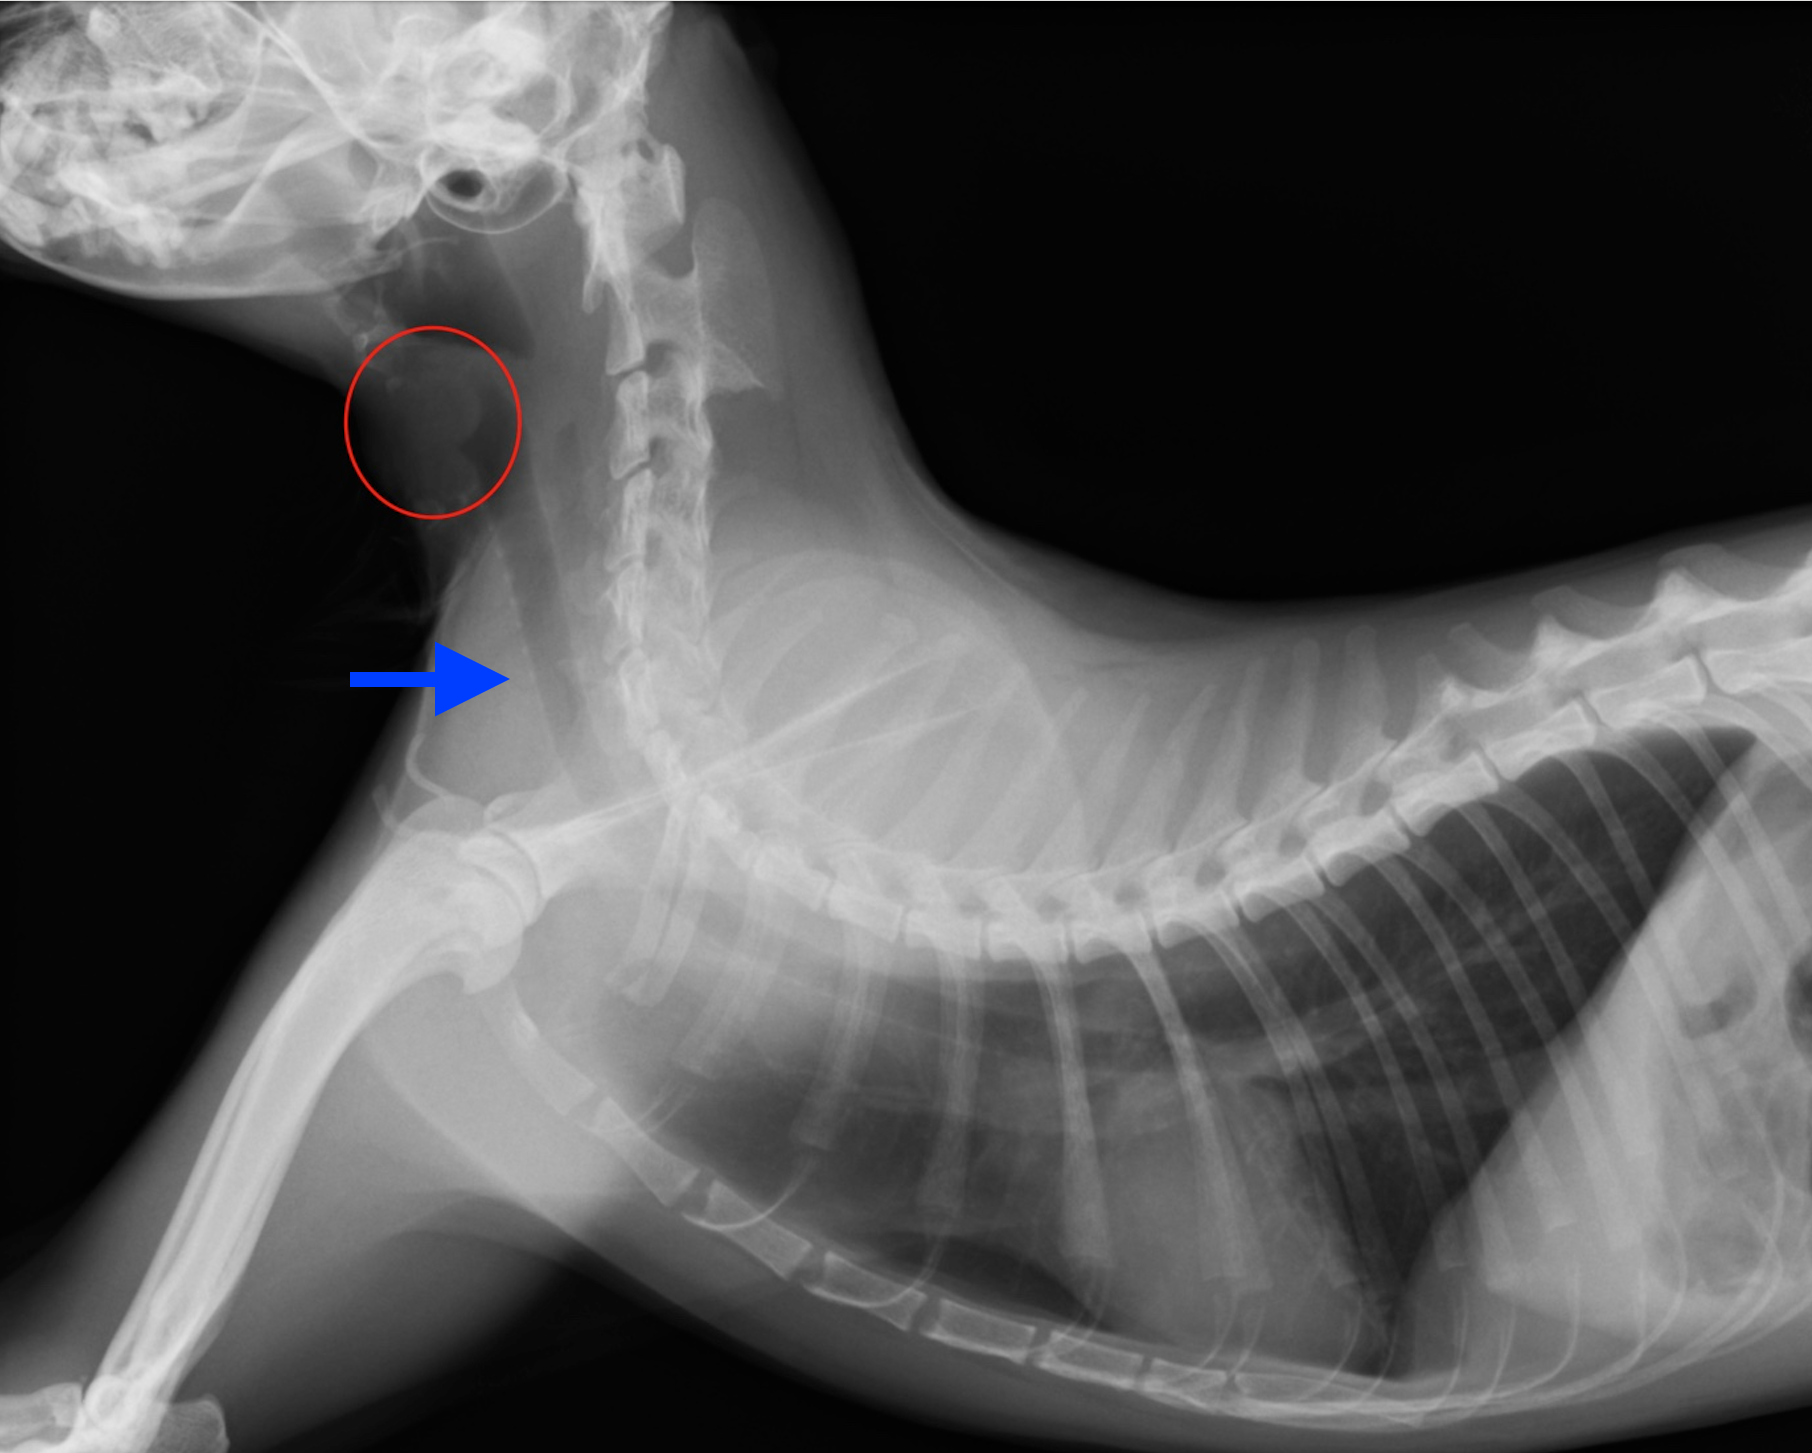

来院時に頸部の皮膚の上から触知ができる1.2cm大の腫瘤を確認しました。触診上で腫瘤は硬く、皮膚からではなく気管やその周囲から発生しているように感じました。

血液検査、ウイルス検査に異常はありませんでしたが、頸部X線検査にて気管から発生する腫瘤を認めました。また頸部の超音波画像検査にて明らかな腫瘤性病変を認めました。

※赤丸の中の白丸に見える部分が気管から発生した腫瘤です。青矢印内の黒く抜けた部分が気管です。